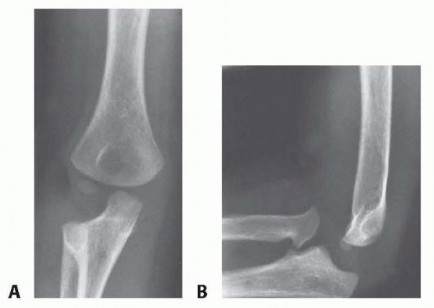

FIG 8 • Congenital dislocation of the radial head in a 7-year-old boy with limited forearm rotation. A. AP radiograph demonstrates an abnormal radiocapitellar line. B. Lateral elbow radiograph also demonstrates an abnormal radiocapitellar line with anterior dislocation of the radial head. The dysplasia of the radial head and hypoplastic appearance of the capitellum are consistent with a congenital etiology despite the anterior radial head dislocation which is more frequently seen following trauma. (From Shah AS, Waters PM. Monteggia fracture-dislocation in children. In: Rockwood and Wilkins' Fractures in Children, ed 8. Philadelphia: Lippincott Williams & Wilkins. In press.)

DIFFERENTIAL DIAGNOSIS

Congenital radial head dislocation (see FIG 8) Nursemaid's elbow (pulled elbow, radial head subluxation) Isolated traumatic radial head dislocationTraumatic elbow dislocation